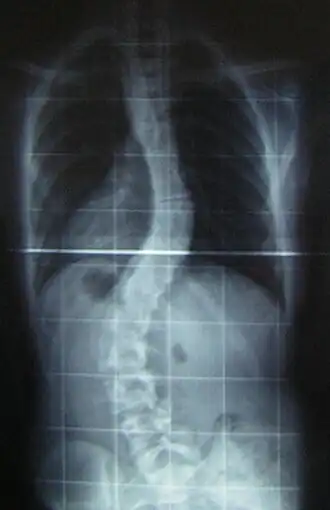

![]() Рентгеновский снимок позвоночника пациента со сколиозом с левосторонним искривлением в поясничном отделе и правосторонним искривлением в грудном отделе позвоночника. | |

Величина искривления позвоночника измеряется с помощью рентгеновского снимка всего позвоночника стоя. Возможны и врождённые рёберные деформации и деформации тел позвонков. С помощью этой информации можно отличить идиопатический и врождённый сколиоз. На рентгеновском снимке в боковой проекции можно также определить, есть ли врождённые деформации в этой плоскости или нарушения нормальных изгибов позвоночника — физиологических кифозов и лордозов.

Схема анализа рентгеновского снимка для определения угла искривления разработана в 50-х годах XX века американским ортопедом Дж. Коббом (англ. John Robert Cobb). Угол искривления, измеренный по рентгеновским снимкам теперь называется «углом по Коббу». Для определения угла деформации на передне-задней рентгенограмме проводят две линии, параллельных замыкательным пластинкам нейтральных позвонков. В точке пересечения этих линий или перпендикуляров к ним измеряют угол сколиоза.